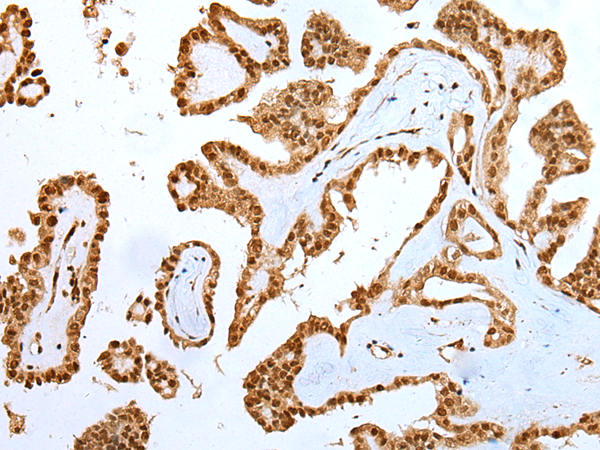

IHC positive control: |

Human gastric cancer and human thyroid cancer |